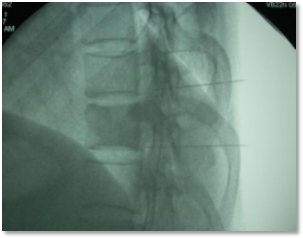

鞘内输注泵植入术是将一根极细的硅胶导管通过穿刺针放入患者的蛛网膜下腔(鞘内),导管的另一端埋藏在患者的皮下,将装有吗啡的电子泵与导管在皮下端相连,泵内的吗啡可直接被注入蛛网膜下腔作用于脊髓的阿片受体,镇痛效果确切,用药量仅为口服的1/300,副作用大大减少。